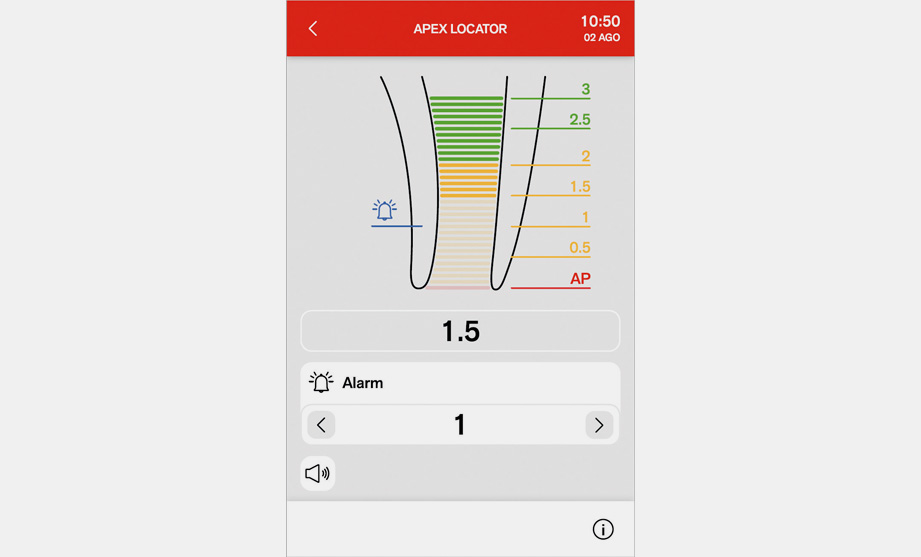

Апекс локатор

Апекс локатор

Расстояние до апекса выводится на дисплей при инструментальной обработке корневого канала. Приближение апекса проверяется программой ENDO. При достижении апекса функция Apex-Stop останавливает вращение микромотора.